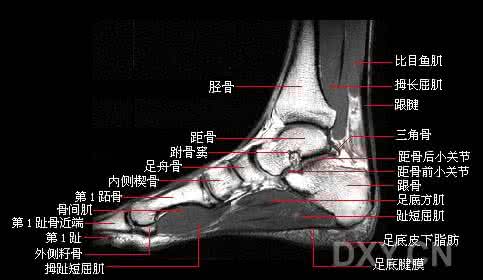

踝关节MRI断层解剖